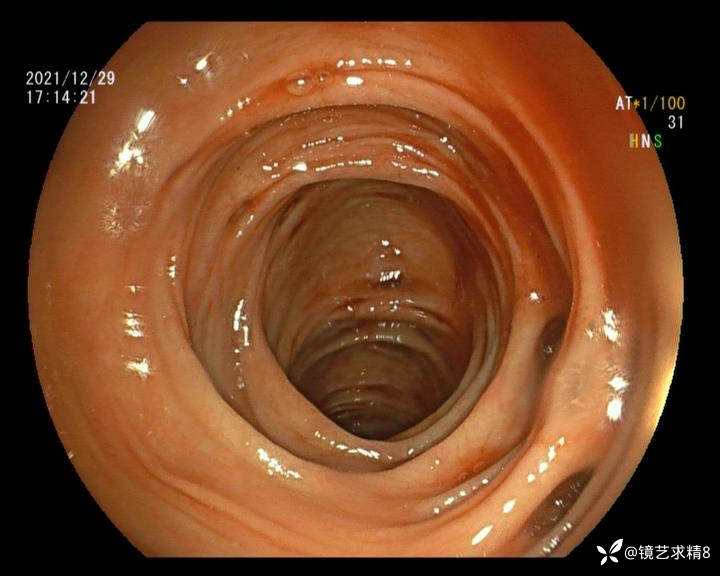

患者以消化道出血入院,胃镜未见异常,肠镜进入乙状结肠就看到很多憩室,同时还看到肠腔用清肠药后移动下来1枚尖锐的枣核,这么多憩室,这个枣核扎入憩室的机会非常大,推测应该是掉入一坑🕳就算出来还会有很多坑🕳🕳🕳等着,掉入憩室内很容易刺破血管,这可能就是消化道出血的原因,继续前进可以看到有一些憩室内翻,还有一些息肉,问题来了,那么多憩室,犯罪分子是抓住了,它在那些憩室内作过案?到达回盲部后挨个冲洗,但憩室大小又不足以把镜头进入憩室内观察,针对有血块的憩室冲洗后可疑出血的以夹子闭合或套扎,取出枣核,如果有锥形透明帽可能钻入憩室精准电凝效果更好,若内镜下操作失败介入治疗成功率更高,经内镜下治疗后观察未再出血出院。